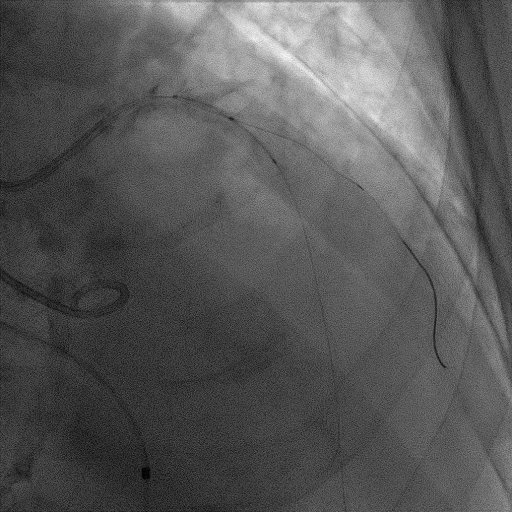

CAG:LAD近中段弥漫钙化,近段80%狭窄,中段90%狭窄,D190%狭窄,中间支近段90%狭窄,右冠近中段弥漫病变,最重狭窄50%。考虑患者胸痛症状可能为冠心病+AS共同作用,以及患者冠脉病变钙化严重,予以旋磨+PCI+TAVR一站式处理。

于中间支植入2.5*18mm支架

1.5mm旋磨头以16万RPM旋磨三次

3.0*15mm球囊后扩张

3.0*15mm球囊预处理LAD近段病变

复查冠脉造影结果满意